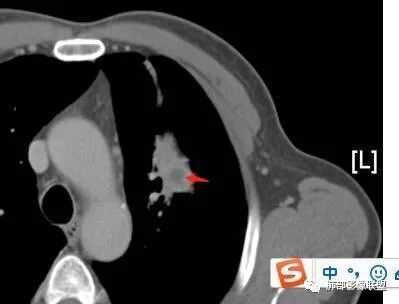

南边:应该是前段吧。前段的支气管怎么样?

张延军:狭窄,阻塞

南边:堵了?狭窄了?

张丽红:扩张,有堵塞?

张延军:狭窄后扩张?

宇宙星空:看远端的话是狭窄了吧,但是近端明显是截断啊,远端的是肺泡腔?

选择:扩张后狭窄

南边:没有堵塞考虑啥?